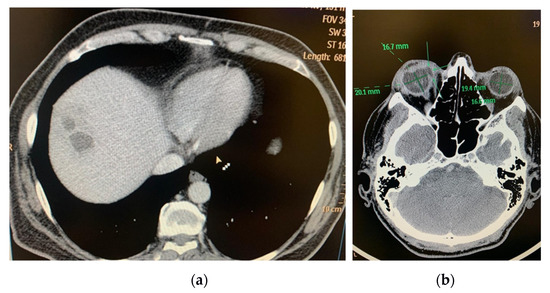

In 25.8% (5–50%) of cases, the septic involvement was bilateral, resulting in permanent vision loss. Bilaterality was encountered in 5–50% of cases in the reviewed studies, in association with multiple septic determinations, such as lungs [38], meninges and CNS, coagulopathy, thrombocytopenia, urinary sepsis (Table 2 and Table 3). There were a total of 78 bilateral cases in a total of 302 patients with EKE and KPLA (25.8%). In all cases with ocular determination, the localization of liver abscess was in the right hepatic lobe (Figure 1 and Figure 2)

Figure 1.

(a) CT exam: multiloculated hepatic liver abscess, right lobe, segment VIII, 50/32/57 mm; (b) CT Exam: Right eye endophthalmitis, eyeball with irregular contour, with a hypodense area in the internal side (at the area of the insertion of the medial rectus muscle), with possible communication between posterior chamber and periorbital space (perforation) (archive of the Ophthalmology Department, Emergency University Hospital Bucharest).